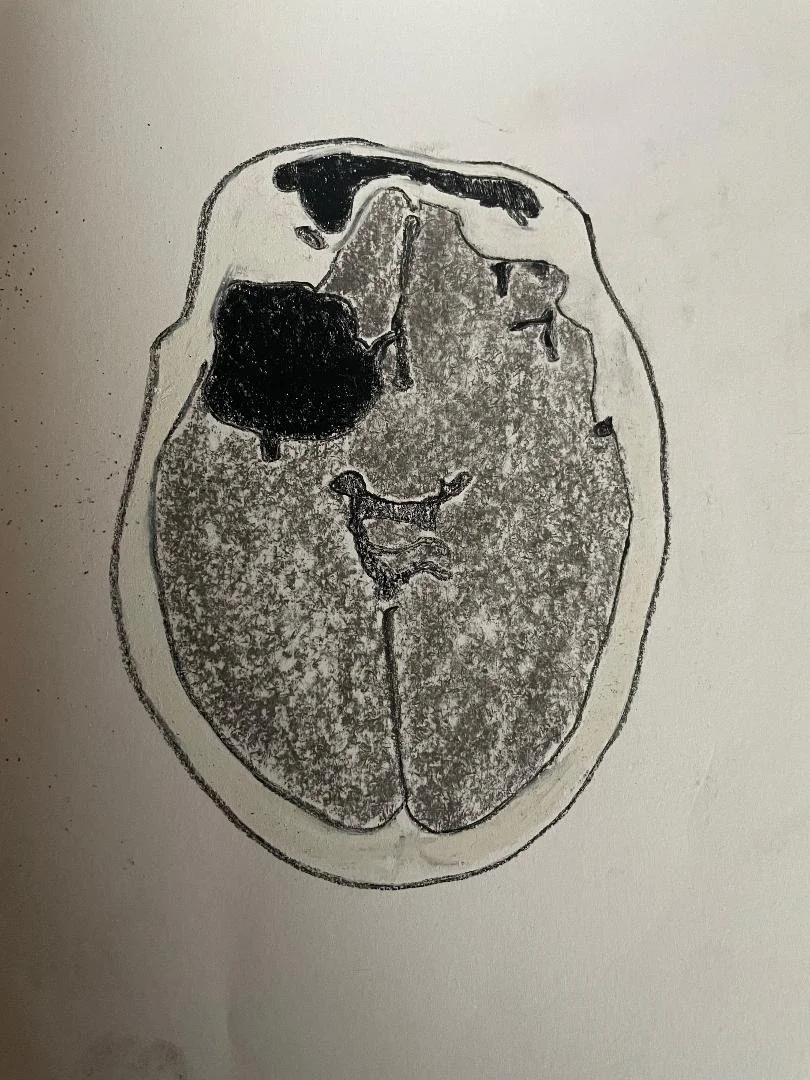

Acute on chronic subdural haematoma